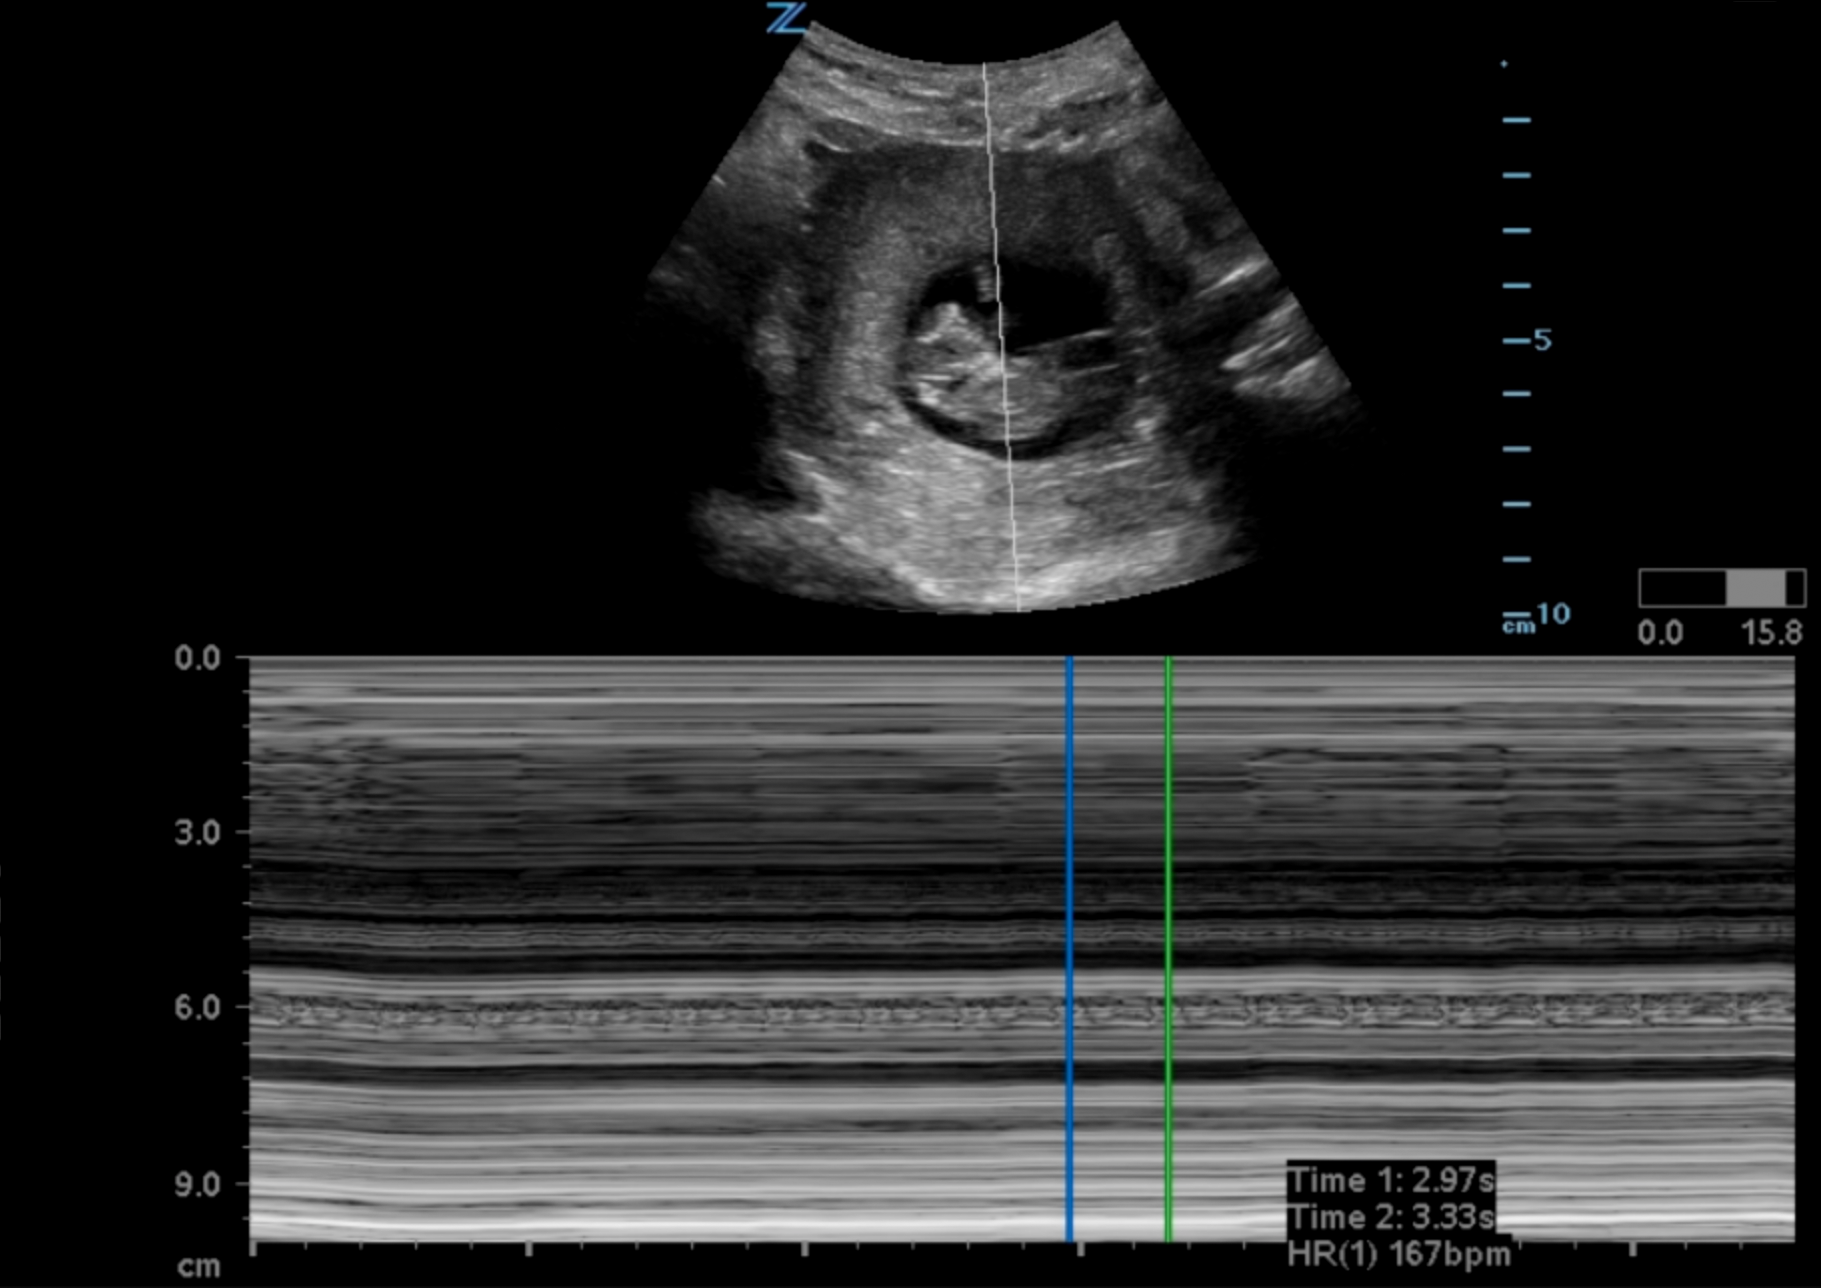

- A Fetal Pole develops weeks 6-7 and a heart rate is visible in the same time frame (Illustration 9, Video 9)

- Fetal heart rate is best by placing an M-Mode spike across the flickering fetal heart and measuring the repeating pattern. (Illustration 9)

- Do not use pulse wave Doppler as it focuses too much energy (heat) on the fetus and goes against the ALARA (as low as reasonably achievable) principle.

- Illustration 9. M-Mode Tracing Fetal Heart Tones